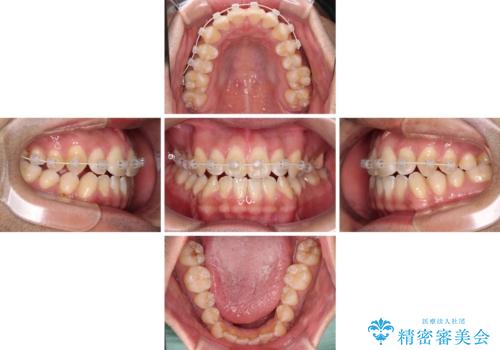

- インビザライン

- 1年11ヶ月

治療の確実性を上げるために、インビザライン開始前に上顎のワイヤー装置にて舌側転位を解消し、その後インビザラインにて矯正治療を行うこととしました。

前歯のデコボコが早めに改善され、スムーズに治療を終えることができました。